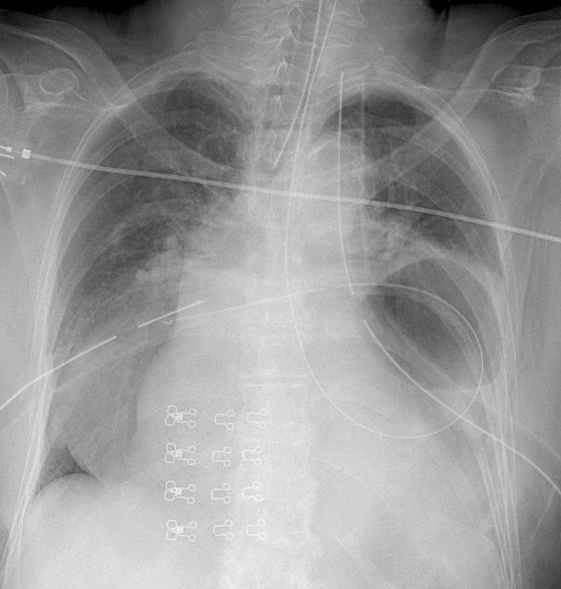

Hiatus Hernia

Case 3 (see CT)